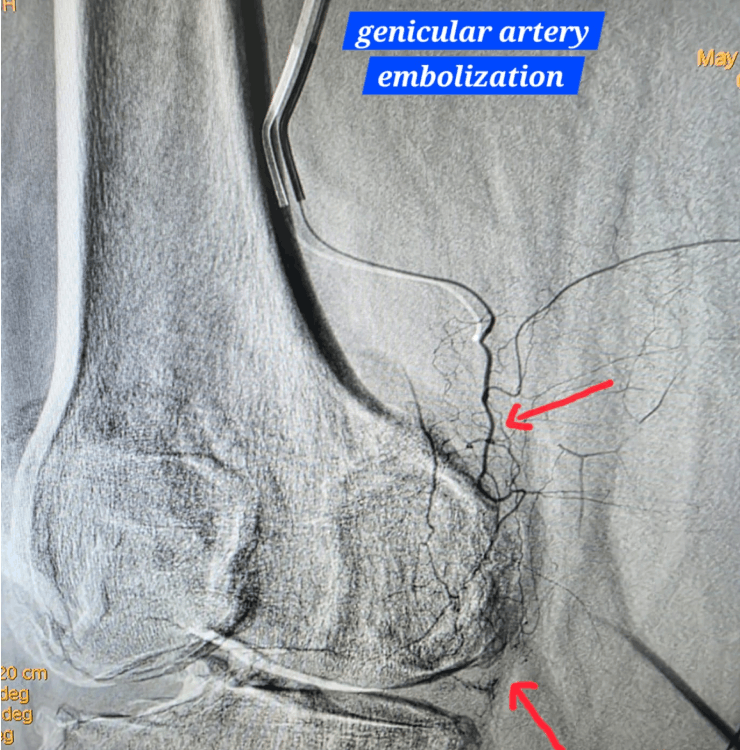

Genicular Artery Embolization (GAE) for Knee Pain

Genicular Artery Embolization is a minimally invasive, image‑guided procedure used to treat chronic knee pain (especially due to osteoarthritis) by targeting abnormal, inflamed blood vessels around the knee. It is typically done through a tiny puncture with local anesthesia and is usually a day‑care procedure.

By reducing abnormal blood flow that sustains inflammation, GAE can help decrease pain and improve function in selected patients who have persistent symptoms despite conservative treatment.

- Genicular Artery Embolization: a thin catheter is guided to the small arteries around the knee under fluoroscopy (X‑ray guidance).

- Targeted embolization: tiny particles are used to reduce abnormal blood flow to inflamed areas, helping reduce pain.